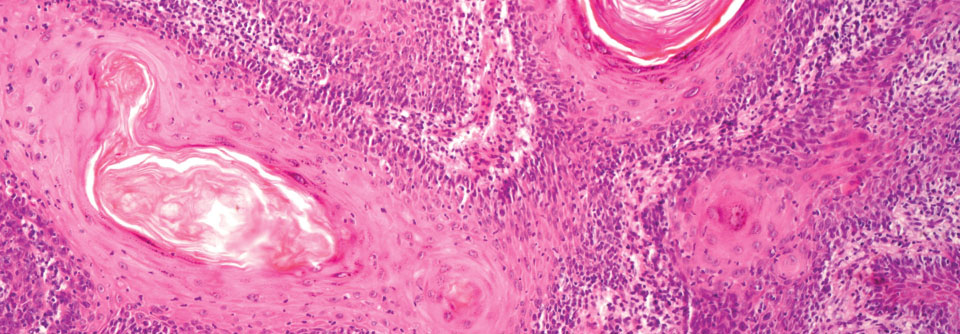

Durch UV-Licht mutiert das Gen für p53, sodass eine aktinische Keratose entstehen kann. Durch UV-Licht mutiert das Gen für p53, sodass eine aktinische Keratose entstehen kann. © Science Photo Library